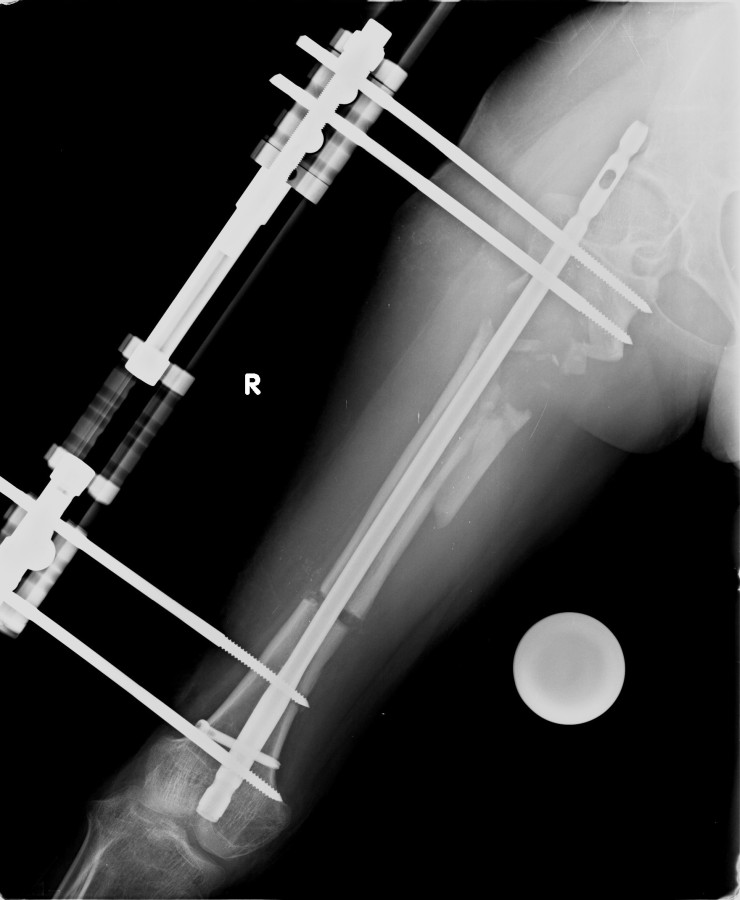

12-14 yaşları arasında Her iki tibiada toplam 10-15cm boy uzatma (iki seviyeli uzatma) Proksimal tibianın varus deformitesini proksimal osteotomi ile düzeltilmesi Distal tibianın varus deformitesi distal osteotomi ile düzeltmesi Distal tibianın varus deformitesi distal osteotomi ile düzeltmesi Boy uzatmanın sonunda lateral kollateral ligamentin gerilmesi Ortalama eksternal fiksasyon tedavi süresi = 8-10 ay